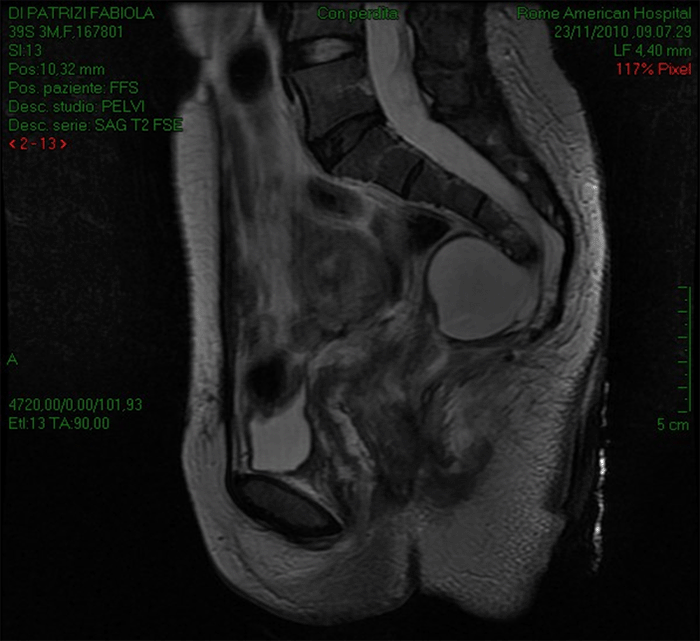

An anal exam revealed the presence of a painful posterior mass. Lab test: WBC 18.800, Hgb 10.1 g/dl ESR 100 mm/h. A pelvic sonogram indicated an 8.5 cm retrorectal mass without defined margins. An MRI of the abdomen was requested and showed the presence of presacral mass above the levator musculature, anterior to the retro sacral fascia, posterior to the rectum compressing a meningocele with a hypoplastic dysplastic coccyx and last sacral elements (Figure 2).

Figure 2. MRI Showing Presence of Retrorectal Presacral Mass Compressing Meningocele. Published with Permission